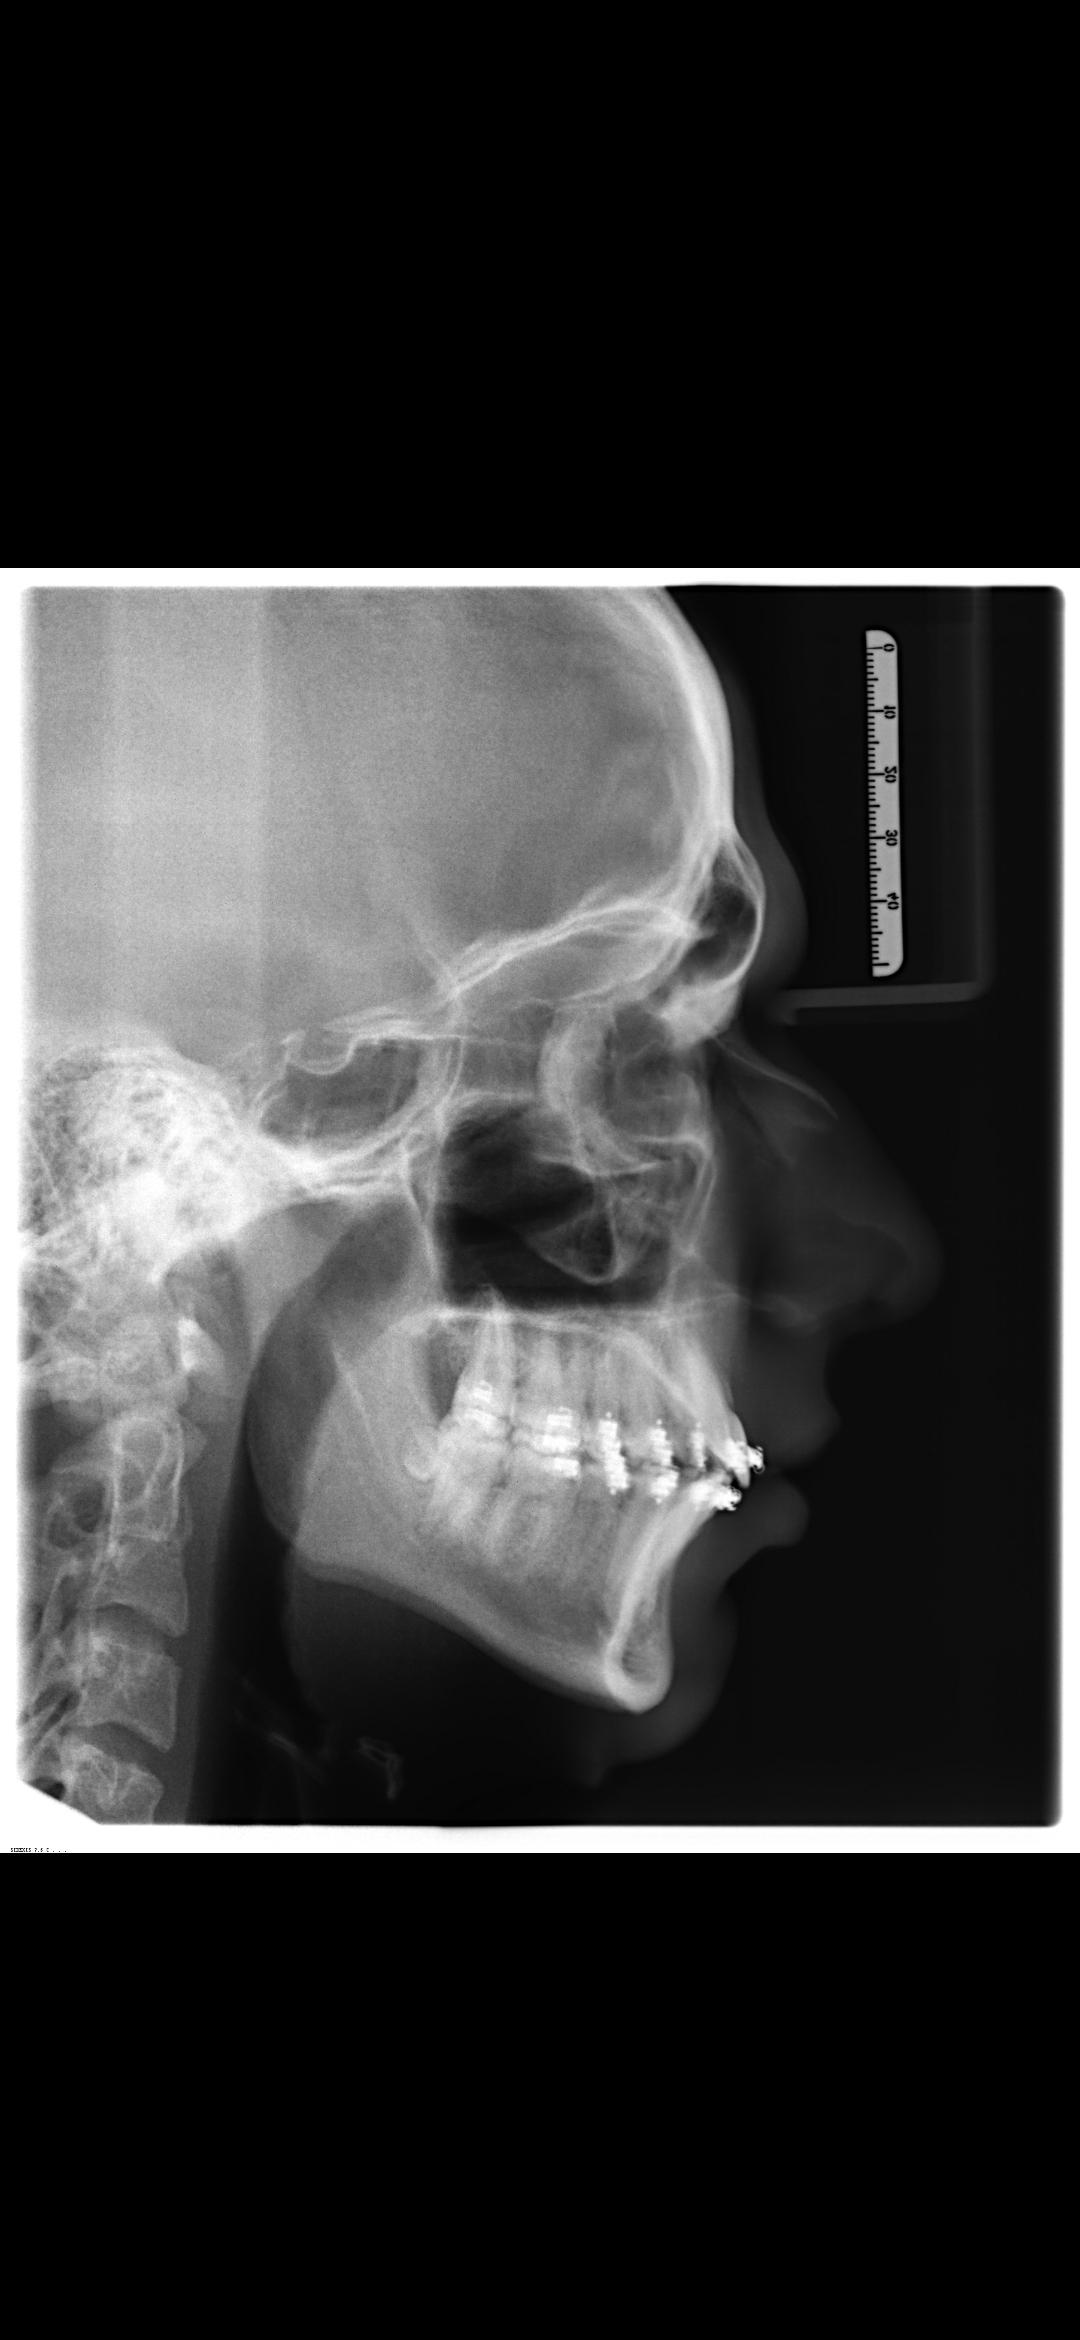

I'm getting bimax next week, and i've talked with friends about if i should get zygoimplants. My surgeon Dr. Kater is very good with implants 8as many people say) but i don't know if he'll give a 17 year old implants...

Is it worth the try? Maybe he thinks im insane and doesen't perform the bimax then...